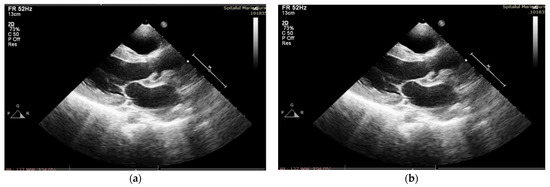

After four days of admission, vesper fever (38.2 C) progressively recurred, and the biological inflammatory syndrome slowly developed. Management was changed to Meropenem at 100 mg/kg/day and Linezolid at 25 mg/kg/day (Vancomycin was replaced with Linezolid due to a severe allergic reaction after the second administration), and this was continued for six weeks. In the first week of treatment, the patient started to develop a significant new diastolic murmur, and echocardiography confirmed spontaneous drainage of the perivalvular aortic abscess, resulting in severe aortic insufficiency and dilation of the left aortic coronary sinus (Figure 1a,b), along with a decrease in LVEF (45%).

Figure 1. (a) TTE PLAX—paravalvular aortic abscess—in the course of formation; (b) after spontaneous evacuation.